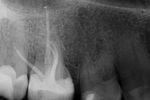

Durch die digitale Volumentomografie lassen sich wichtige zusätzliche diagnostische Informationlassen gewinnen. Die räumliche Darstellung erleichtert die Behandlungsplanung und gibt Sicherheit in der Therapie.

Die digitale Volumentomografie wird bei folgenden Verdachtsdiagnosen empfohlen:

– apikale Veränderungen bei Vorliegen klinischer Auffälligkeiten, wenn diese auf zweidimensionalen Aufnahmen nicht detektierbar bzw. räumlich korrelierbar sind

– Wurzelfrakturen, da diese aus rein mathematischen Gründen sicherer identifiziert werden als mit zweidimensionalen Aufnahmen

– Perforation, insbesondere Stiftperforationen

– dentales Trauma

– interne und externe Wurzelresorptionen

– erschwerte Begleitumstände wie komplexe Anatomie des Wurzelsystems

– Gefährdung anatomischer Nachbarstrukturen

– intrakanalär frakturierte Wurzelkanalinstrumente